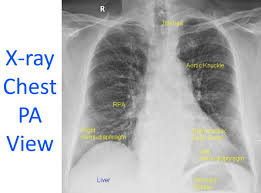

X-RAY CHEST PA VIEW

Standard and Routine Imaging for the Chest Cavity

An X-ray chest PA view, also known as a posterior anterior chest X-ray, is a standard and routine imaging procedure used to examine the organs and structures within your chest cavity. Here's a comprehensive explanation of this X-ray technique:

The PA view, where PA stands for posterior (back) anterior (front), means the X-ray beam originates from behind you and travels through your body to a detector placed in front of your chest. This positioning offers several advantages over an anterior-posterior (AP) view, where the X-ray beam comes from the front:

- Clearer view of the lungs: The PA view offers a more unobstructed view of the lungs, as the bulky structures like the breastbone and shoulder bones are spread apart during the procedure, allowing for better visualization behind them.

- Reduced heart size magnification: Since the X-ray beam travels through a lesser amount of tissue to reach the heart in a PA view, the heart size appears less magnified on the image compared to an AP view. This provides a more accurate assessment of actual heart size.